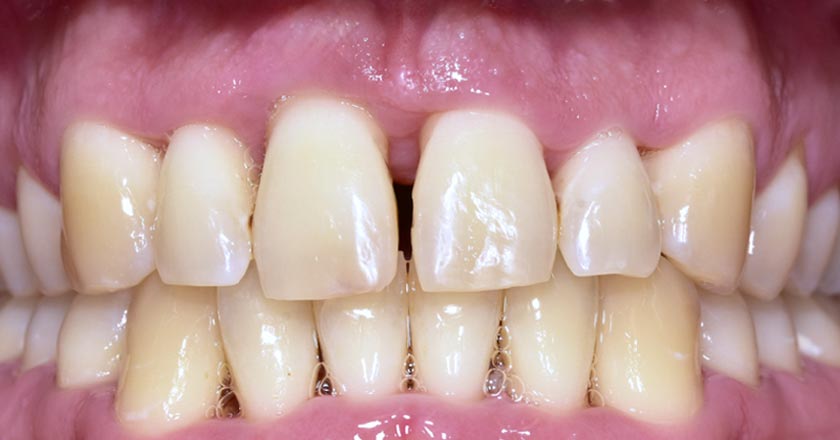

Gum Disease - Before And After

Gum disease scaling and root planing – before treatment

Gum disease scaling and root planing – after treatment